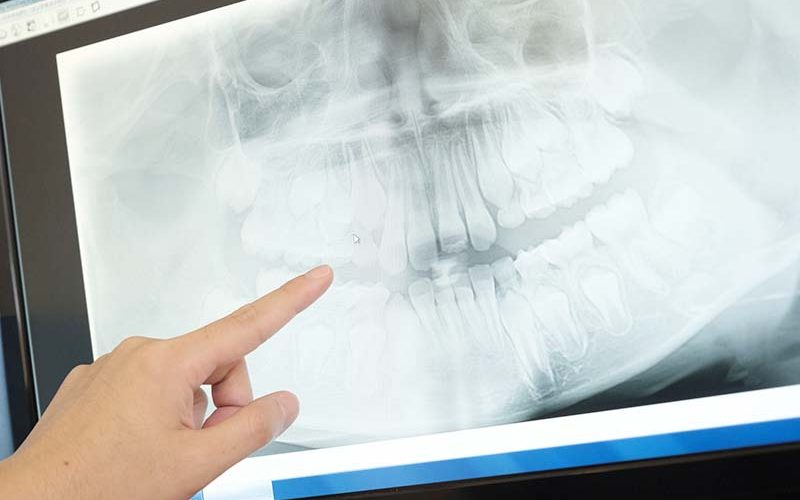

先天欠如歯や埋伏歯は、見た目だけでは正確な判断はできません。必ずレントゲン撮影を行い、歯の本数と位置を確認する必要があります。上記の内容に当てはまったり、気になることがあれば、一度当院へお気軽にご相談ください。